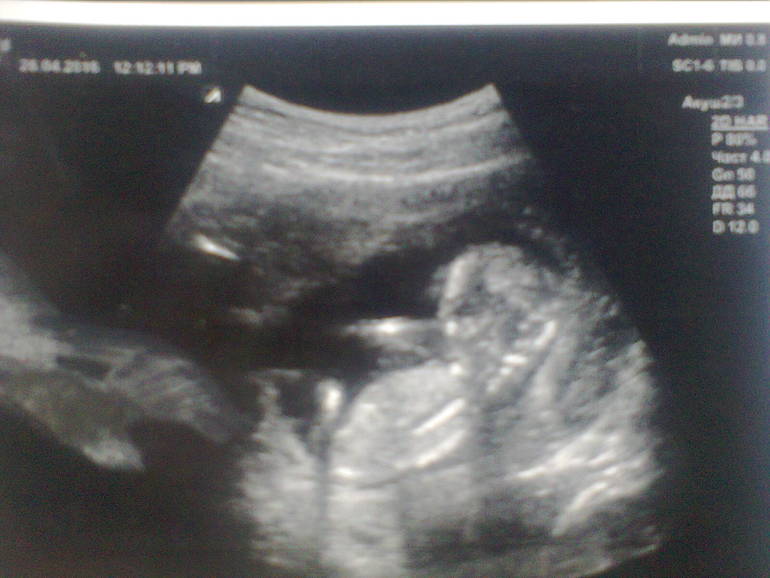

Последнее (и единственное) мое УЗИ было на 6 неделе, и я очень переживала что немного затянула его до 13 недели. Все чудесно! Все развивается в срок 13+2, я видела и слышала сердечко своего чуда, наблюдала как он отталкивает ножками и ручками датчик Узи. Мы с мужем счастливы!